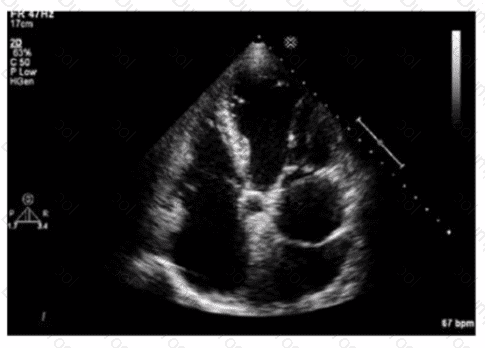

What is the regional wall motion assessment of the two-chamber view displayed in this video?